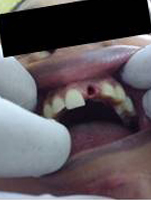

Placement of Implant

Single Tooth Implant